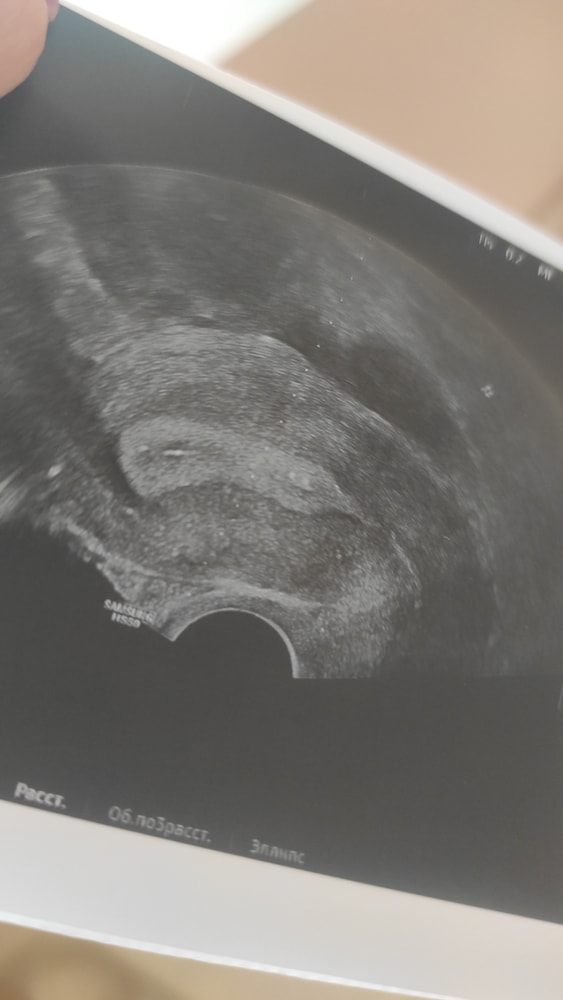

Протоколы ЭКО (Все о них, все об этом периоде+Гиперстимуляция)Дорогие девочки, смотрю на снимок после переноса и вижу что в отличие от первого раза где точечки на распечатанном УЗИ при подсадке были в середине матки сейчас они прям у самого низа матки где цервикальный канал

Мог ли доктор подсадить так низко , на след день дпп1 у меня выпали два крупных круглых кровяных сгустка в яичном белке круглой формы я в смятении могли ли просто выпасть эмбрионы и почему они подсажены так низко?

Могли бы вы посмотреть прислать фото куда вам подсадили эмбрион на вашем успешном крио? У кого были успехи с посадкой так низко? Я очень переживаю. Эмбрион после пгд и это просто немыслимо почему он так низко подсажен

напишите фамилию врача и куда вам подсадил. Я расстроилась очень. Доктор отвечает что на фото просто не видно место подсадки но это не первый мой крио и мне всегда сажали выше в центр матки тут скажите честно ошибка врача?